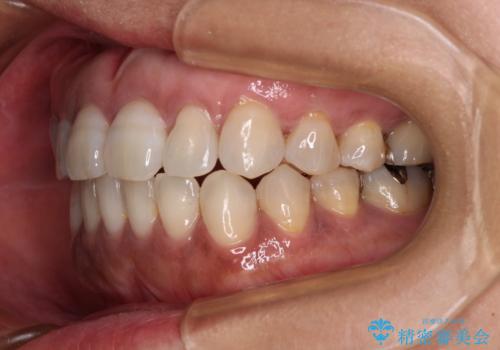

極端な上下前歯の開咬を改善 オープンバイトのインビザライン矯正

治療前に、いくらインビザライン矯正がオープンバイトを得意としているとは言え、さすがに限界があるだろうと思っておりましたが、前歯でレタスが噛めるまで改善することができました。

顔の印象も大きく変わり、患者様には大変満足していただきました。